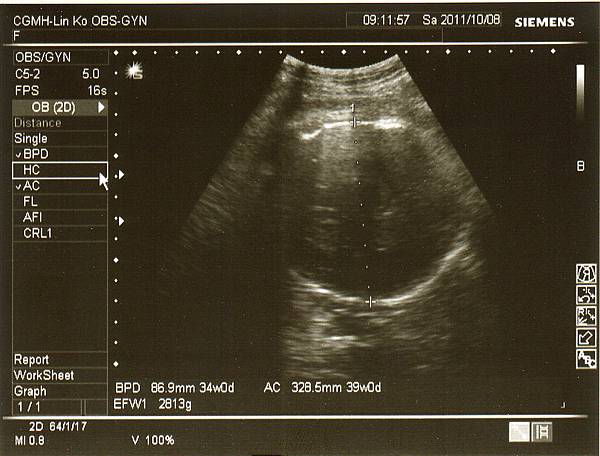

但是寶寶也才增加約200克,現在寶妹約2190克,

醫生說小了一些些,不過羊水量和心跳都很正常,